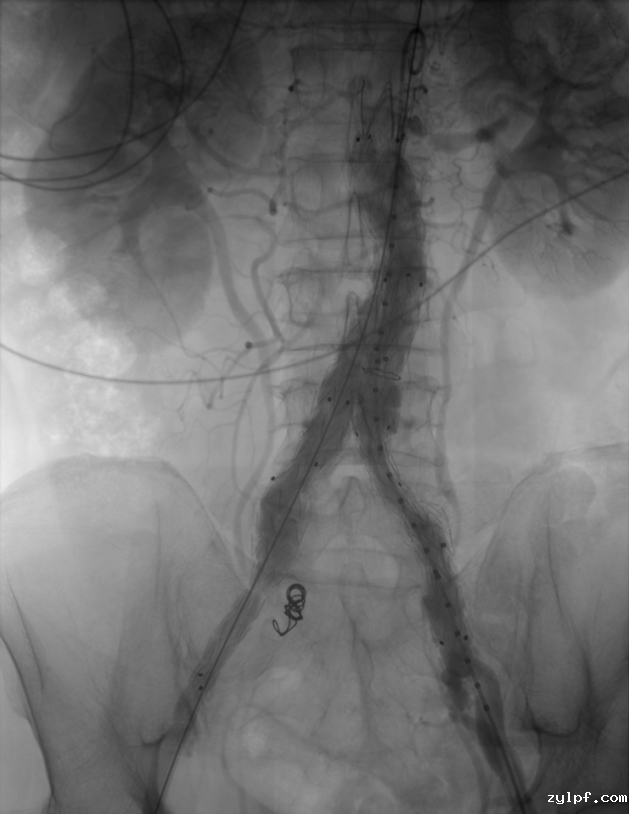

图片 4.png

▶ 腹主动脉造影,腹主动脉中下段呈瘤样扩张